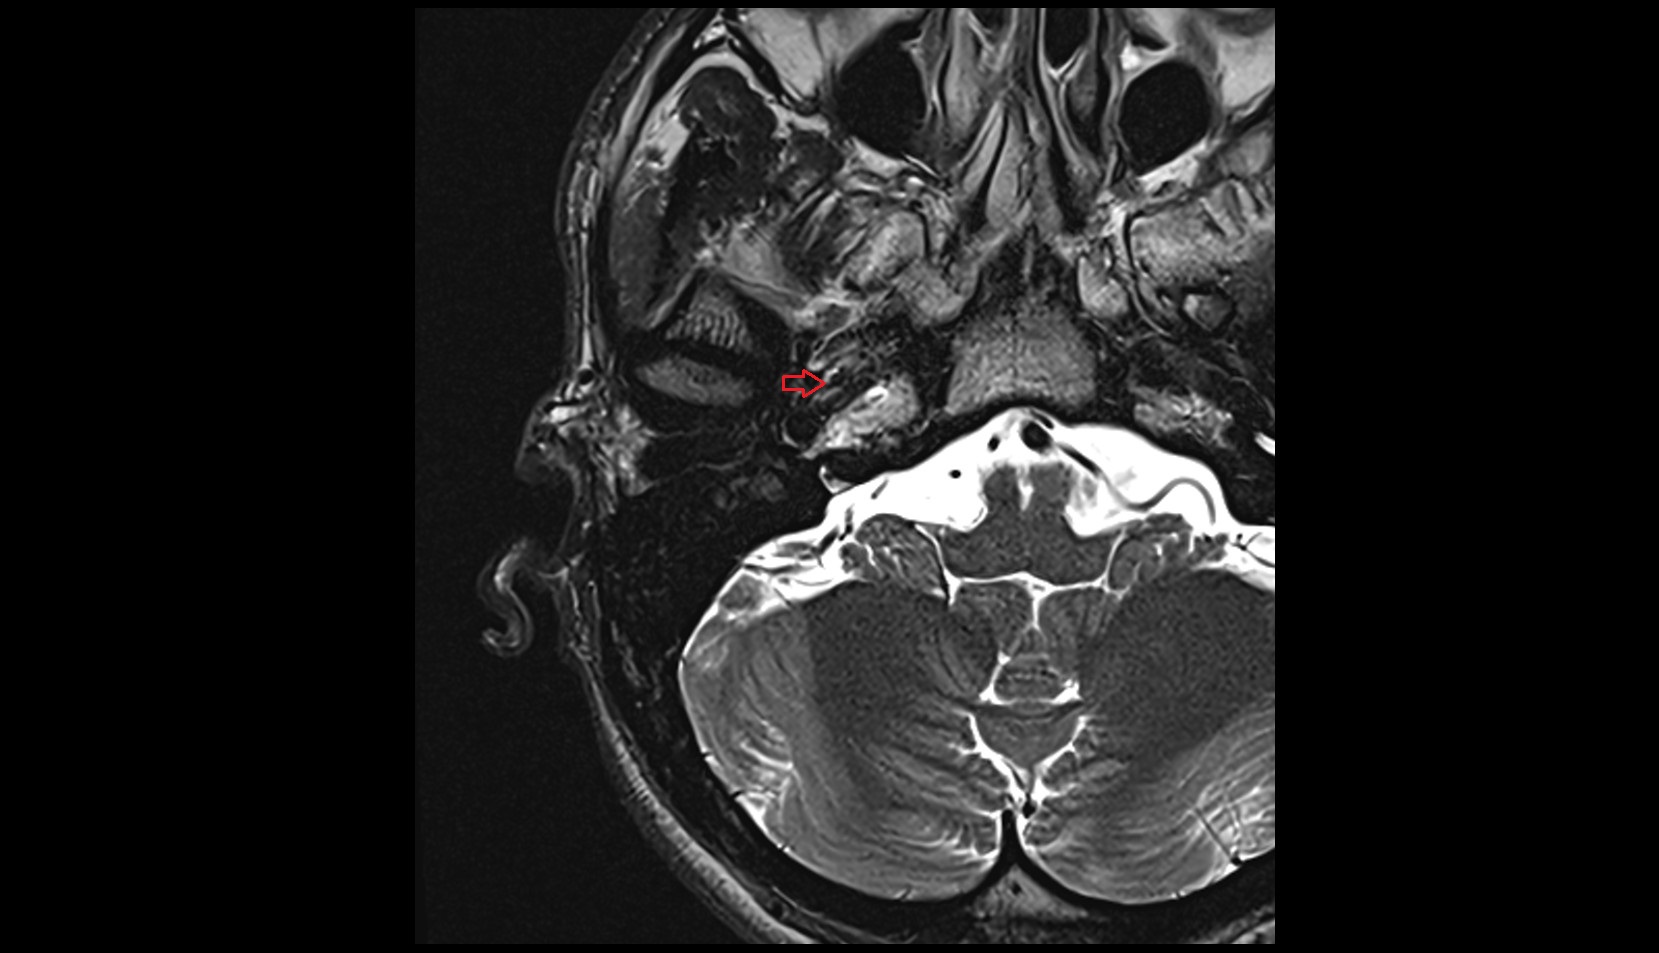

- Lateral aperture of fourth ventricle (foramen of Luschka)